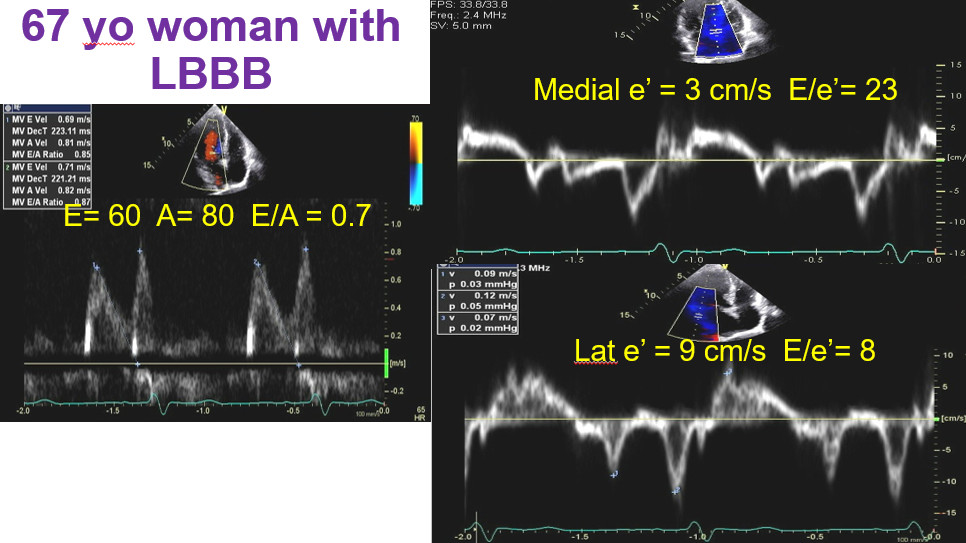

#4/7. In most patients, I use medial or septal e' velocity rather than averaging unless there is >30% difference between medial and lateral e' as shown in figure from LBBB patient. This patient has normal FP. Lateral e' is about 25% higher than medial e' in normal setting.